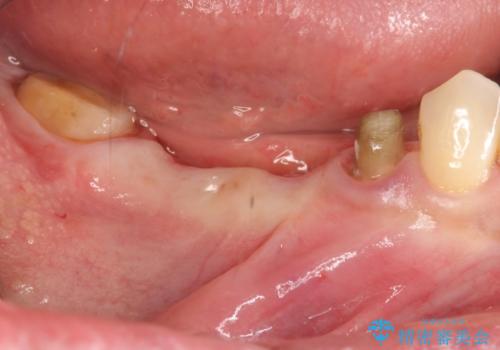

- 銀歯だらけの口の中に嫌気がさし、改善を求めて来院されました。

設計に無理のある長期的に良好な状態が保てるとは思えないブリッジを除去し、インプラントを用いた補綴計画を立てます。